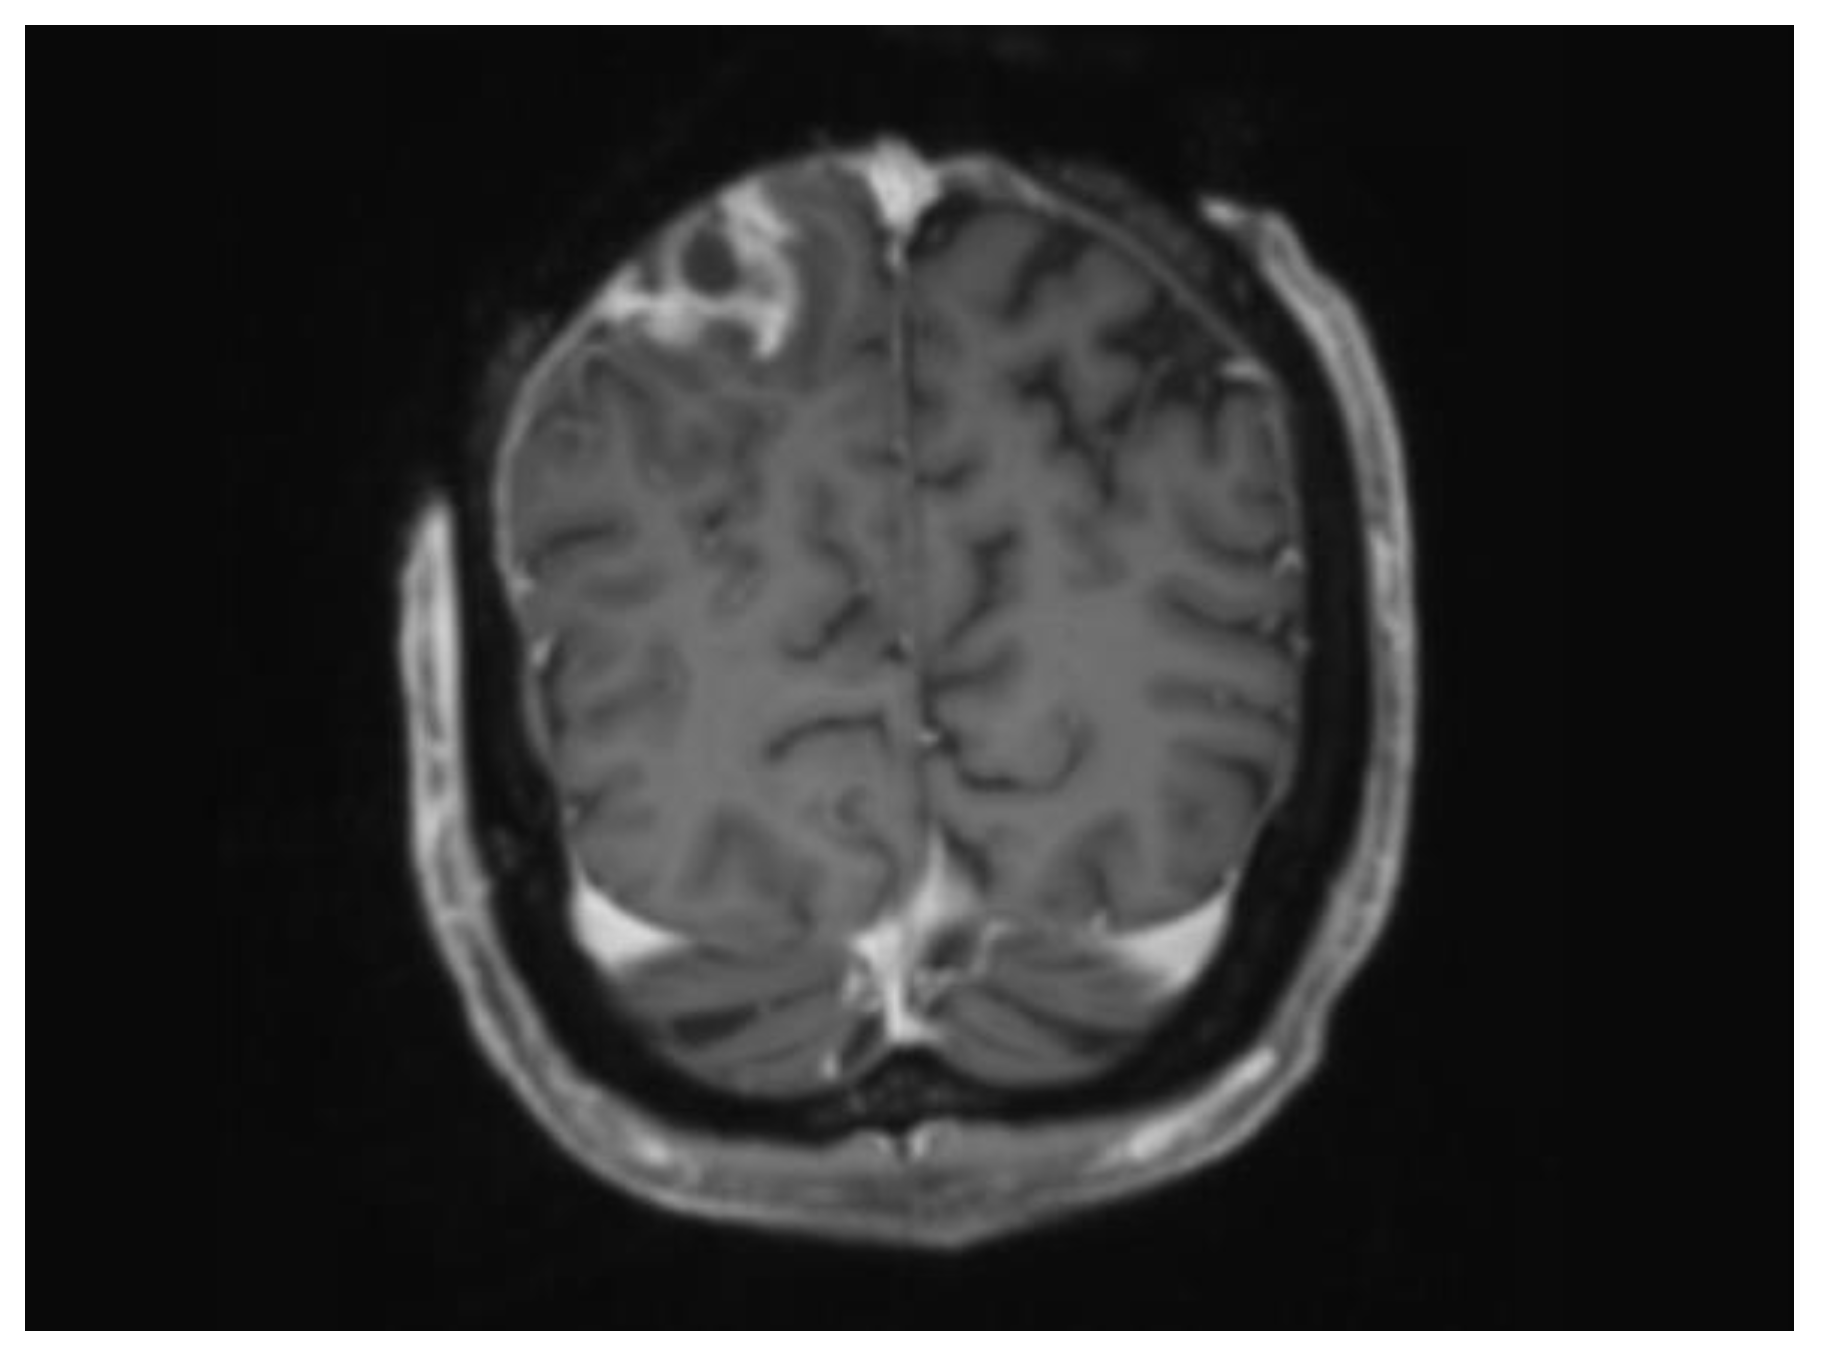

| Normal MRI Brain and Spine. | |

| 27 | CT Head demonstrating loss of bone marrow signal and a peripherally enhancing lesion highly suspicious for an underlying abscess. These findings were consistent with MRI imaging. |

| 40 | MRI Brain revealing a superficial fluid filled collection in the subcutaneous tissue over the right parietal lobe. MRI spine showed symmetric T2 abnormalities within the cervical cord posterolaterally. |

| 47 | MRI confirming interval reduction in size of the subcutaneous collection. No evidence of intracranial re-accumulation. |